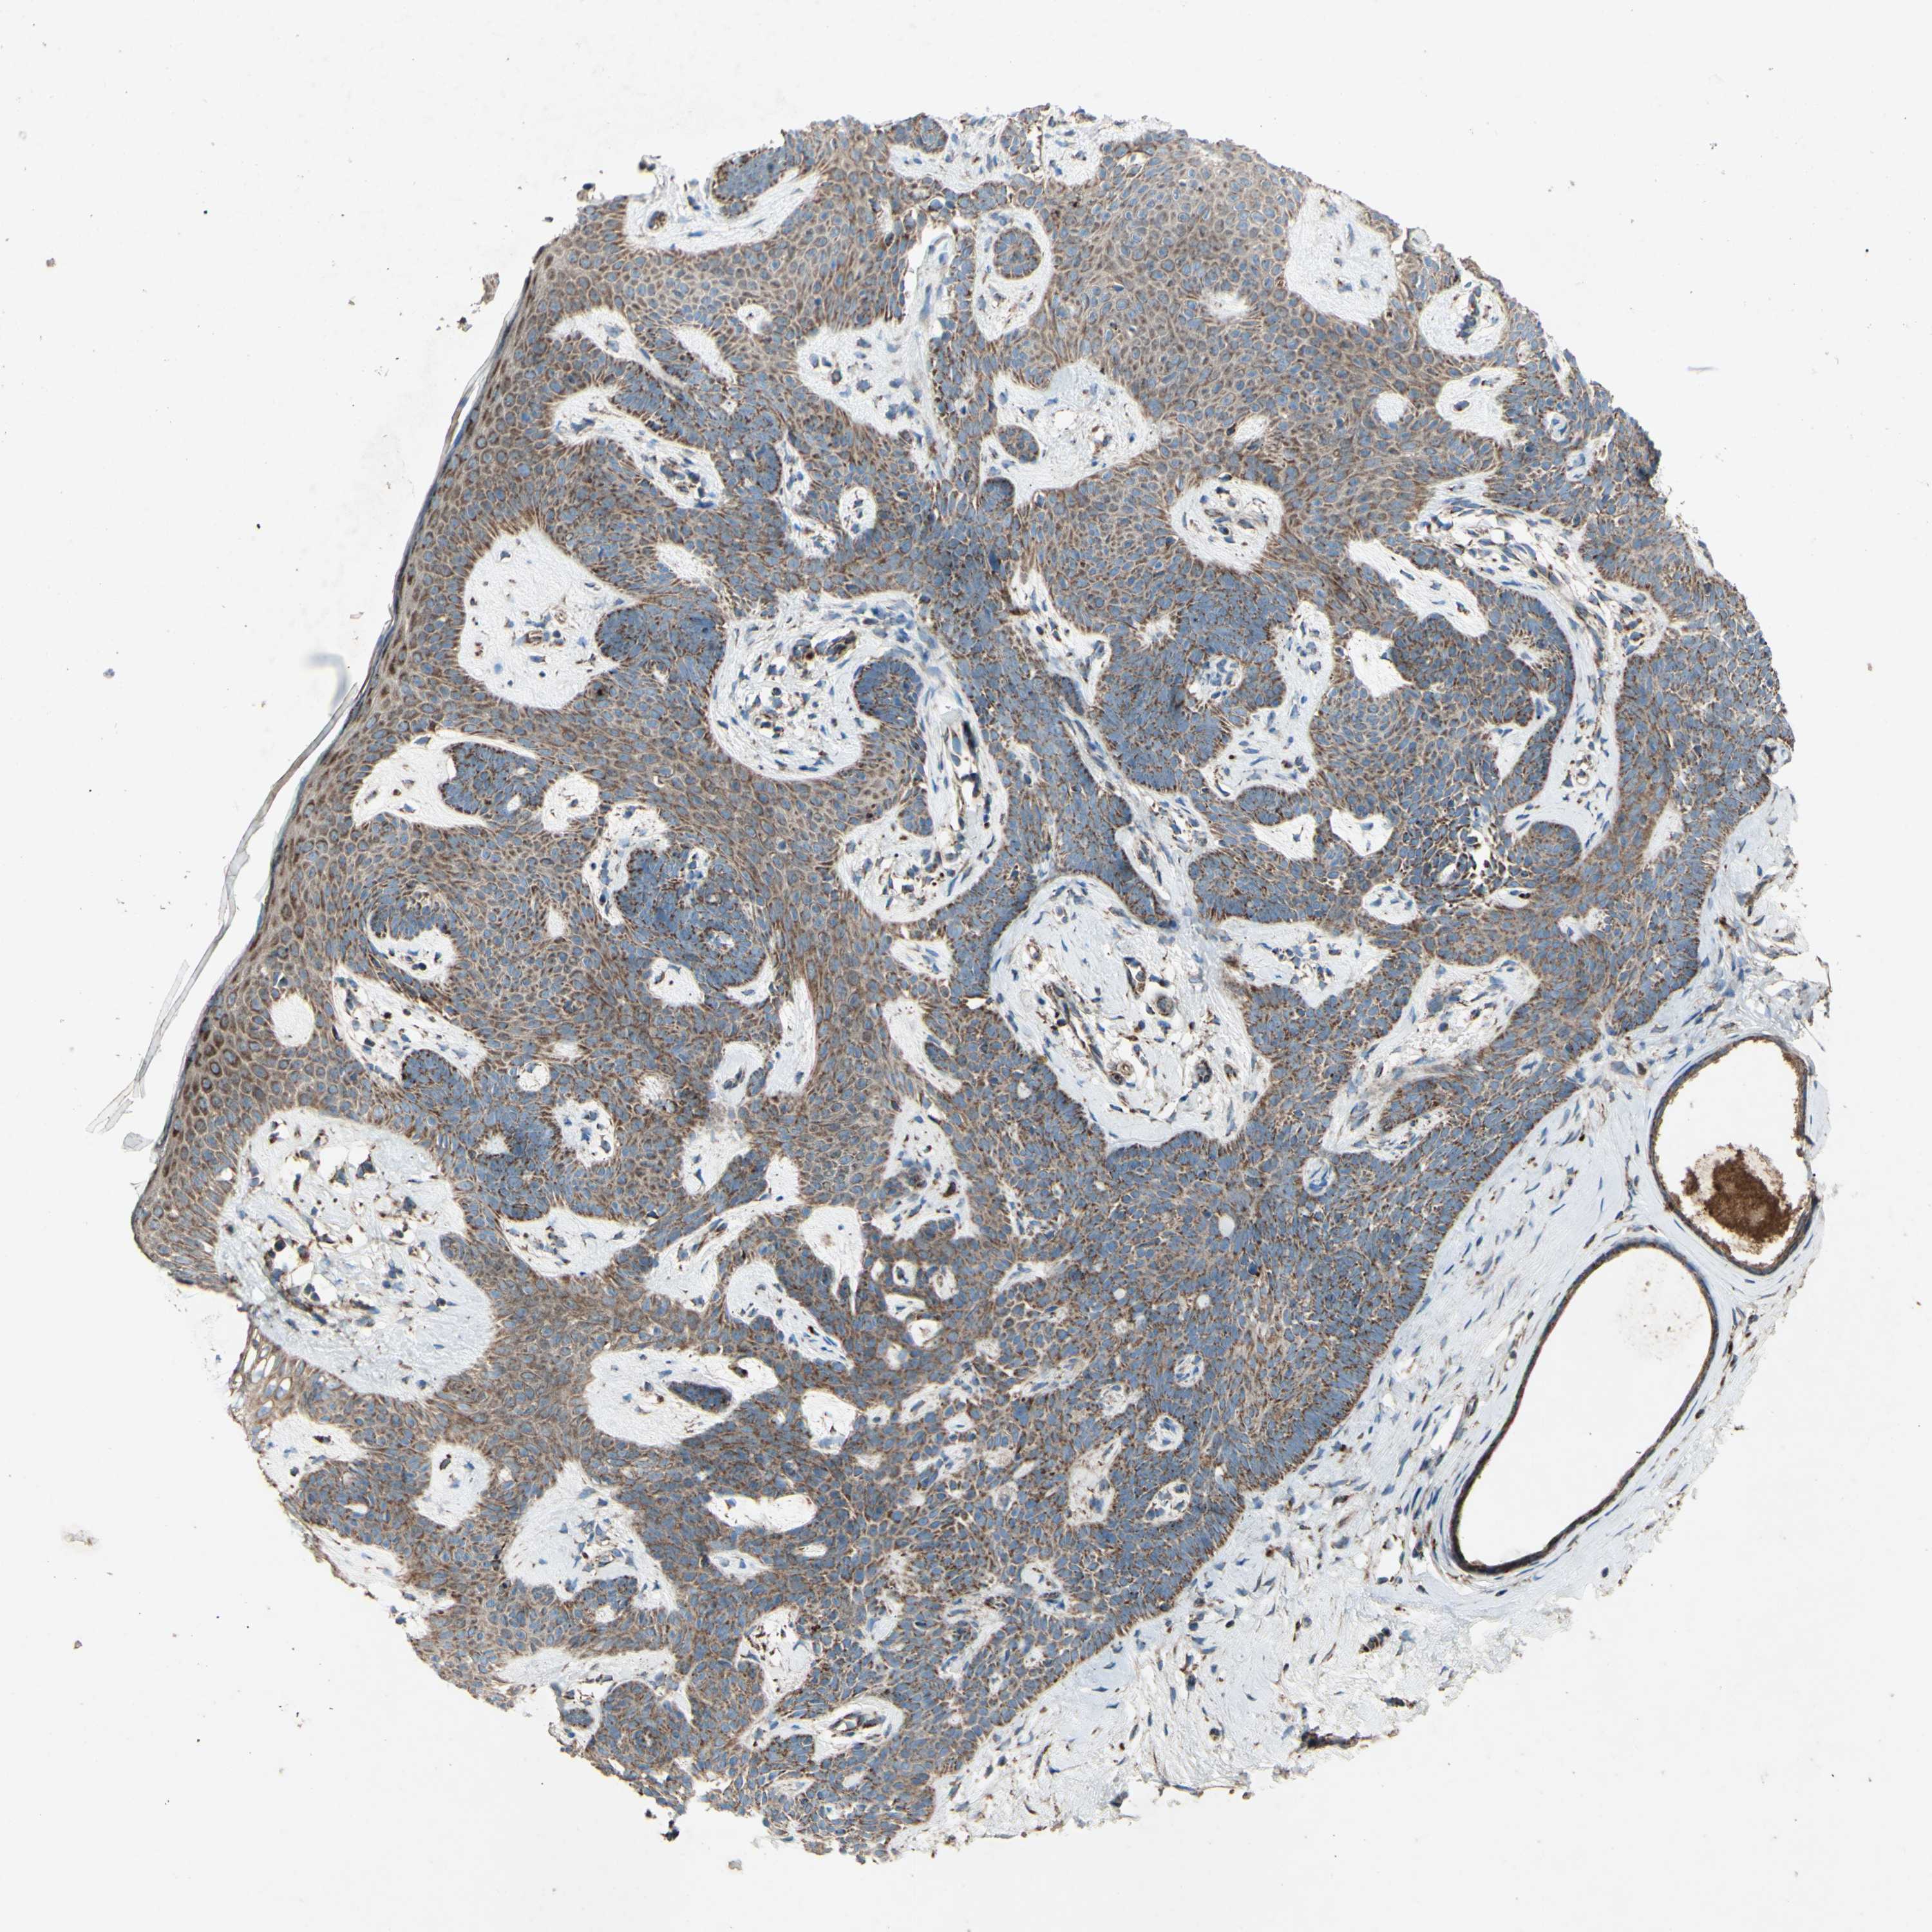

SKIN CANCER - Protein expressioni

A mouse-over function shows sample information and annotation data. Click on an image to view it in a full screen mode. Samples can be filtered based on level of antibody staining by selecting one or several of the following categories: high, medium, low and not detected. The assay and annotation is described here.

Each image is clickable and will lead to virtual microscopy that enables deeper exploration of all samples and also displays staining intensity scores, fraction scores and subcellular localization as well as patient and tissue information for each sample.

Antibody HPA010687

Staining

High

Medium

Low

Not detected

Intensity

Strong

Moderate

Weak

Negative

Quantity

>75%

75%-25%

<25%

None

Location

Nuclear

Cytoplasmic/membranous

Cytoplasmic/membranous,nuclear

Squamous cell carcinoma, NOS

Squamous cell carcinoma, metastatic, NOS

Basal cell carcinoma

Papilloma, NOS